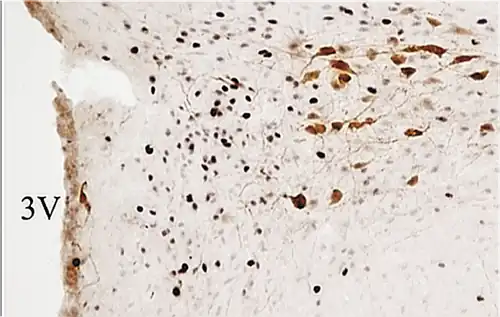

PaMP= parvocelular medial;

PaLM=magnocelular lateral.

3V= tercer ventrículo.